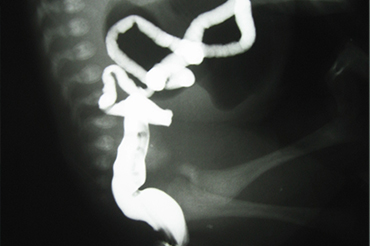

Atresia Intestinal

Neonatal y Lactante